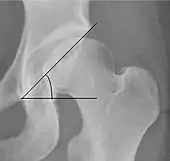

| Tönnis angle | ![]() |

Slope of the sourcil (the sclerotic weight-bearing portion of the acetabulum) | 0 to 10°

|

| Caput-sourcil angle[12] | ![]() |

Superior to the Tönnis angle in cases without joint space narrowing or subluxation.[12] The medial point of the sourcil is defined as being at the same height as the most superior point of caput femoris. | −6 to 12°[12]